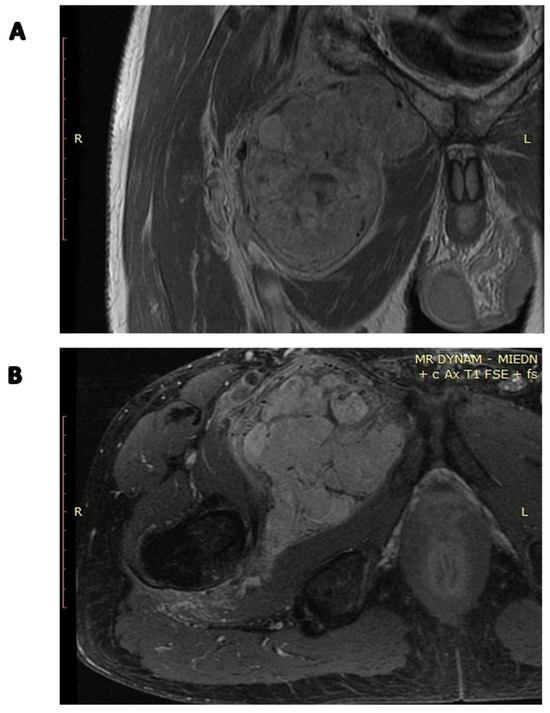

4. Diagnosis

5. Clinical and Radiological Differential Diagnosis